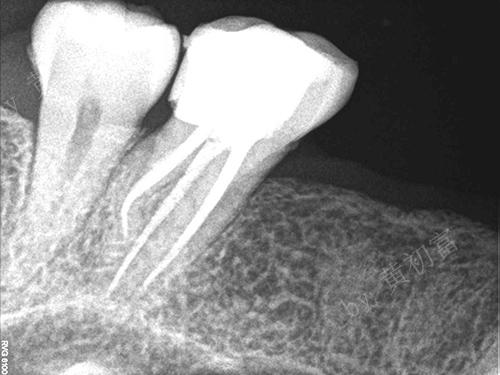

急性牙髓炎案例(一)

性别:女

年龄:59

主治医生:王琳勇

所在门诊:宁德中富口腔

主诉:左侧后牙遇冷热刺激剧痛3天

治疗方案:26根管治疗后数值天聪

术前